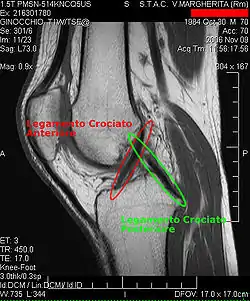

Le ligament croisé postérieur est situé dans la fosse intercondylaire du fémur.

En haut il se fixe sur la face latérale du condyle médial du fémur. Il descend en croisant dans les plans frontal et sagittal le ligament croisé antérieur. Il est séparé de ce dernier par une bourse séreuse interligamentaire. Il se termine sur l'aire intercondylaire postérieure du tibia.

Le ligament croisé postérieur forme avec le ligament croisé antérieur le « pivot central » de l'articulation fémoro-tibiale. Ils s'opposent à un déplacement du tibia vers l'arrière par rapport au fémur, appelé traditionnellement tiroir postérieur du tibia ainsi qu'à une rotation excessive[1].